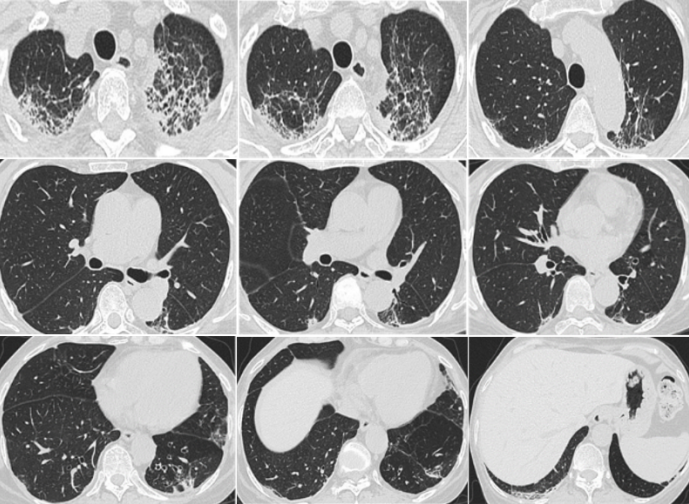

与家属沟通后行气管插管+全麻气管镜下靶肺区刷检+灌洗+冷冻肺活检术,BALF+膜刷检+冷冻肺活检组织NGS(双流程)结果示:DNA测序回报曲霉属(序列数87,RNA测序回报耶氏肺孢子菌(序列数20。组织活检病理:下均见肺泡上皮萎陷,部分肺泡腔内充盈红细胞,间质纤维组织增生伴较多淋巴细胞及少量中性粒细胞浸润,周围散在泡沫样细胞。免疫组化结果:CD31(血管+),D2-40(淋巴管+),偏光(+)。特殊染色结果:网染(-),Masson(+),弹力纤维(+),刚果红(-)5)

图片

5  肺部TBCB HE染色及免疫组化

根据上述结果行MDT,接合临床特征和特殊用药史诊断为药物性肺病,胺碘酮引起的肺部损伤。在原有支持对症治疗基础上,修正治疗方案为甲基强的松龙240 mg静脉泵入,序贯甲泼尼龙口服维持治疗。3个月后复查血液相关异常指标均恢复正常,复查胸部CT可见肺部病灶基本吸收,胸腔积液吸收6)

6  患者治疗3个月后复查胸部CT

此例患者在入住ICU拟诊感染性病变后第一时间经气管镜肺泡灌洗完善感染相关检查,在病原诊断阴性情况下,再次行气管插管后介入取材,同时获取下呼吸道黏膜、灌洗液及组织标本,应用多种检测方法平行送检,检测结果相互印证,排除肺部感染,结合MDT明确诊断,更改治疗方案后获得了很好的疗效,充分显示了呼吸介入诊断技术联合多种病原检测技术在疑难危重弥漫性肺部疾病鉴别诊断中的价值。